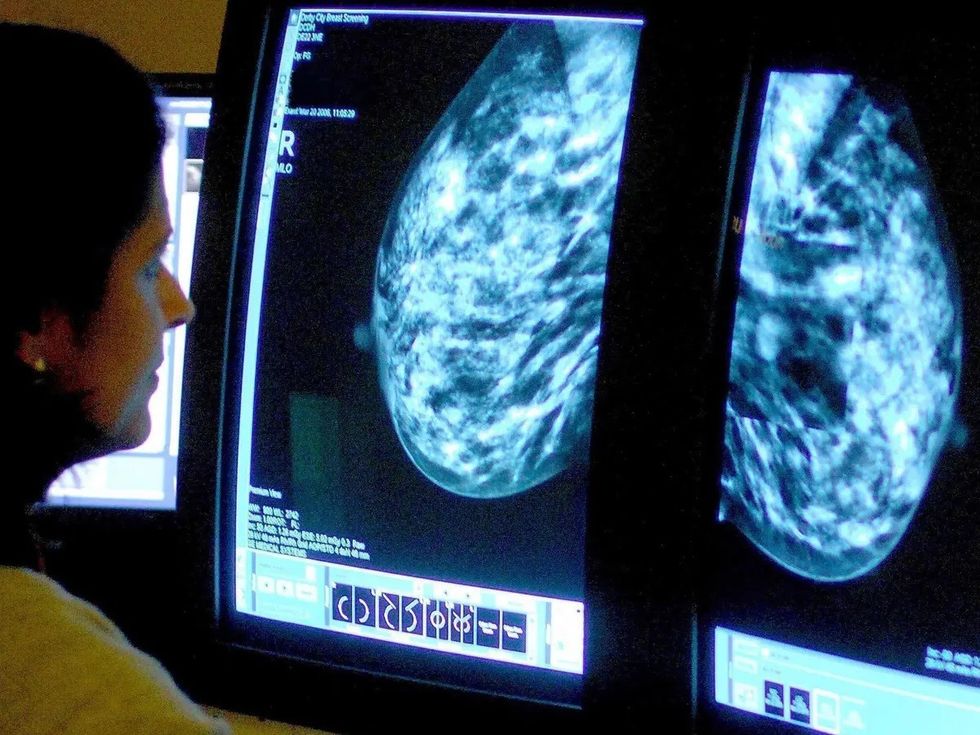

Përdorimi i inteligjencës artificiale në depistimin e kancerit të gjirit është i sigurt dhe pothuajse mund të përgjysmojë ngarkesën e punës së radiologëve, sipas studimit më gjithëpërfshirës në botë të këtij lloji

Rezultatet paraprake nga një studim i madh sugjerojnë se ekzaminimi i inteligjencës artificiale është po aq i mirë sa dy radiologë që punojnë së bashku, nuk rrit rezultatet false dhe pothuajse përgjysmon ngarkesën e punës.

Studimi është vlerësuar nga ekspertët si shumë pozitiv dhe ata janë të mendimit se inteligjenca artificiale mund të ndihmojë në përshpejtimin e diagnostikimit te gratë për ta zbuluar kancerin në një fazë të hershme dhe për të shpëtuar më shumë jetë.